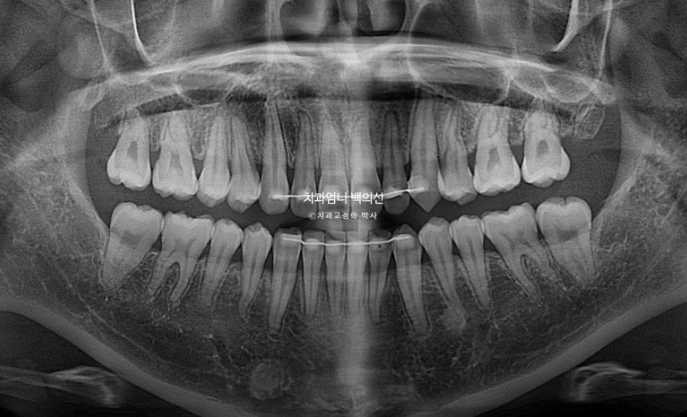

1년 9개월간의 치료기간동안 치근흡수는 일어나지 않았습니다.

치아 뿌리 평행도도 좋습니다.